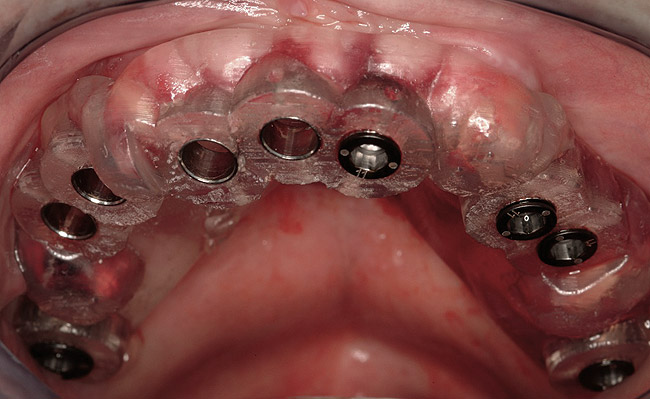

Figure 1  Note wide flap reflection necessary for titanium mesh removal and implant placement. The apical extent of the flap is necessary not only to remove the mesh but also two fixation screws that need to be placed at a safe distance from the apices of the adjacent teeth.

Figure 1

Figure 12  Flapless, computer-guided implant placement was performed. A transmucosal healing mode was chosen, with the placement of standard healing abutments.

Figure 12